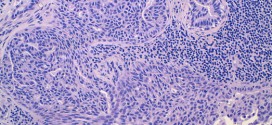

Desde el punto de vista clínico, las lesiones cutáneas de la micosis fungoide evolucionan a través de tres estadios: manchas o parches, placas y tumores. Las manifestaciones iniciales son bastante inespecíficas y en estas fases es difícil establecer el diagnóstico con seguridad. La micosis fungoide es un linfoma de células T de la piel (cutánea) de bajo grado, representando el …